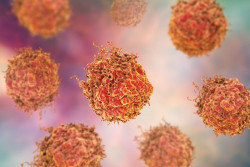

La cirugía es un tratamiento viable para los pacientes con cáncer de páncreas, especialmente tras la quimioterapia

Los pacientes con cáncer de páncreas en estadio II que reciben quimioterapia seguida de una intervención para eliminar la parte cancerosa del órgano, viven casi el doble de tiempo que los pacientes que reciben quimioterapia sola, según una nueva investigación publicada en línea en el `Journal of the American College of Surgeons`.